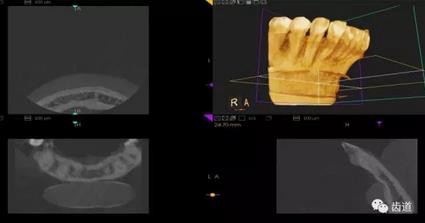

三)種植修復(fù)

CBCT在牙種植修復(fù)中的應(yīng)用。種植前利用CBCT對患者的牙床進行檢查,可精準(zhǔn)判斷牙槽骨的寬度、厚度及高度、骨的密度、重要的顏面神經(jīng)、血管和鼻竇位置等。臨床醫(yī)生不僅可以在計算機直觀的看到牙槽骨的立體影像,還可以切換不同的視角來觀察硬組織之間的位置關(guān)系,在手術(shù)方案中避開危險區(qū)域,保證手術(shù)的安全性。臨床醫(yī)生還可以利用CT數(shù)據(jù)進行數(shù)字模型重建,配合軟件預(yù)先做好手術(shù)模板,使種植手術(shù)更安全快捷,避免在種植手術(shù)過程中不慎破壞神經(jīng)、鼻竇等解剖結(jié)構(gòu),導(dǎo)致顏面神經(jīng)麻痹、鼻竇炎等并發(fā)癥的發(fā)生。

1、下頜骨種植牙前測量準(zhǔn)備影像

2、上頜骨種植牙前準(zhǔn)備影像